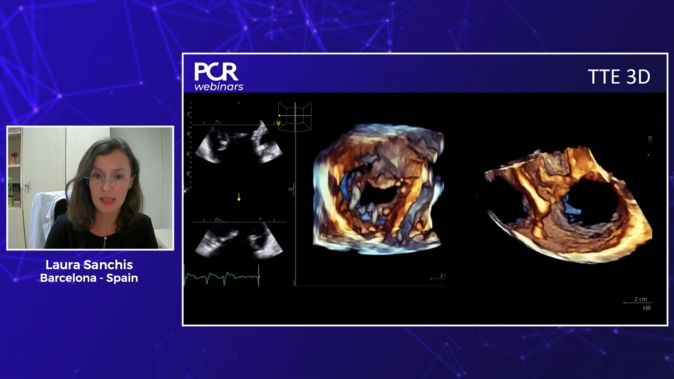

Advancing the management of tricuspid valve disease: diagnosis, imaging, and intervention

01 Feb 2025 – From PCR Imaging Valves Madrid 2025

How to best image the atrioventricular valves?

14 May 2024 – From EuroPCR 2024

This session, in collaboration with the PCR Tricuspid Focus Group, aims to provide a comprehensive understanding of how to image the atrioventricular valves (mitral and tricuspid) to assess their anatomy and pathology. It covers the step-by-step evaluation of the mitral and tricuspid valves using transesophageal echocardiography...